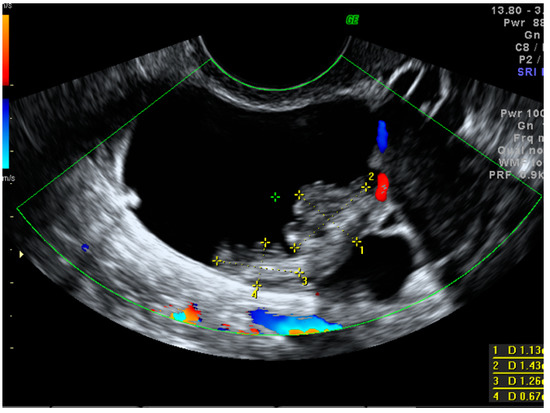

| Largest solid component (mm) Median (25th–75th percentile) (min–max) | 0 (0–17) (0–102) | 19 (0–29) (0–190) | 31.5 (9.5–40.5) (0–102) | 0.0006 BEN vs. MAL 0.002 |

| Papillation size Median (25th–75th percentile) (min–max) | 0 (0–11) (0–24) | 4 (0–17) (0–52) | 0 (0–17) (0–35) | 0.16 |

| Height of the largest papillary projection (mm) Median (25th–75th percentile) (min–max) | 0 (0–8) (0–21) | 3 (0–11) (0–45) | 0 (0–10) (0–26) | 0.21 |